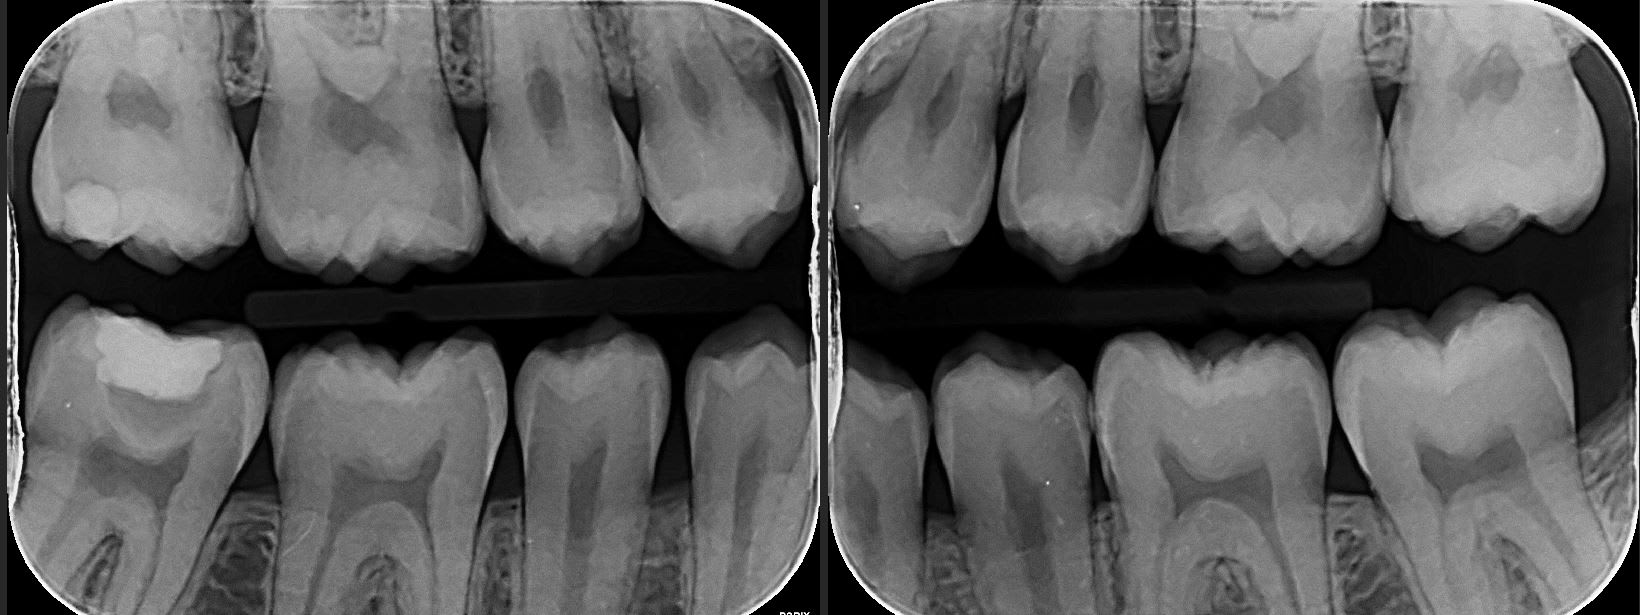

ci joint les radios, pour la 47 il ya une résine avec un fond de cavité

Ils veulent toujours une pano dans leur dossier : ils ont du en faire une ou en prescrire ne et ont vu la 47.

Que ferais tu en voyant une image de la 47? prendrais tu le risque d'envoyer le patient en Opex pendant des mois?

Explicite ton diagnostic avec des radios pour traiter de la stabilité clinique de ton coiffage pulpaire.

Meme si la 47 est a l'equilibre dentine tertaire-cavité-pulpe, la proximité pulpaire rend quad meme difficile la notion de stabilisation a long ou moyen terme.

Le dentiste de l'armée a jugé les risques potentiels que présenterait cette 47 .Il n'aurait pas du parler a proprement de carie, mais de risques non nuls de pulpite a moyen terme, pas top en opération.

Pas tres facile a classer, cette 47. Concretement, soyez honnetes, on vous dit "un an sur une ile deserte sans soins médicaux possibles" , vous vous feriez traiter endodontiquement cette 47 ou non avant de partir?

Le mec a certainement mis de la biodentine sur la 47 . Si la restauration supérieure n’est pas infiltrée, je ne vois pas pourquoi on s’amuserait à dépulper une dent asymptomatique

C est quoi ce fond de cavité qui est totalement radio-transparent ???

Clairement... C est a peine moins radio opaque que la dentine. La c est quand même très très radio clair...

Pour moi la c est de la biocarix... ;)

Non ça c est la projection de la convexité de la racine distale qui crée une zone radioclaire.

oui pourquoi pas. De toute façon ça ne coûte rien de démonter la restauration de 47 et de voir si il y a bien de la biocarix

Surtout qu après tu peux faire une jolie endocouronne.

Une belle endo + endocouronne et là il peut aller l esprit tranquille en opex avec un traitement a l apex.